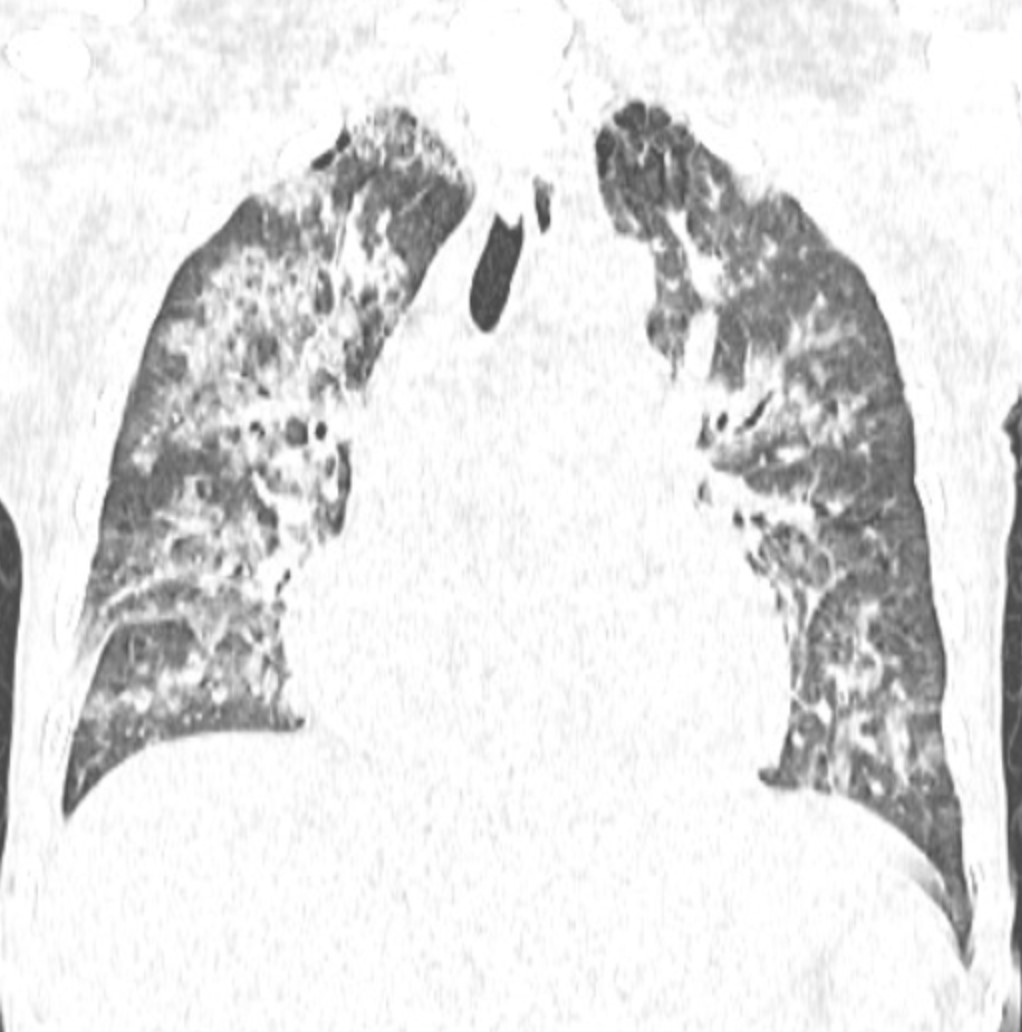

Đến ngày 24/10, trong một lần truyền huyết tương tiếp theo để xử lý tình trạng đông máu, người bệnh xuất hiện khó thở tăng dần chỉ sau khoảng 15-20 phút truyền, SpO₂ từ 97% còn khoảng 88-90%, huyết áp tăng, tĩnh mạch cổ nổi, nghe phổi có ran ẩm hai bên.

Chụp CT scan phổi thấy hình ảnh phù phổi cấp, các xét nghiệm khác phù hợp với chẩn đoán Quá tải tuần hoàn liên quan tới truyền máu (TACO). Kíp trực đã dừng truyền, cho thở oxy, đặt tư thế ngồi và dùng thuốc lợi tiểu, nên người bệnh cải thiện triệu chứng.

Ảnh: Phim chụp Xquang phổi của bệnh nhân C.Đ.C (21/10) và CT scan (24/10)